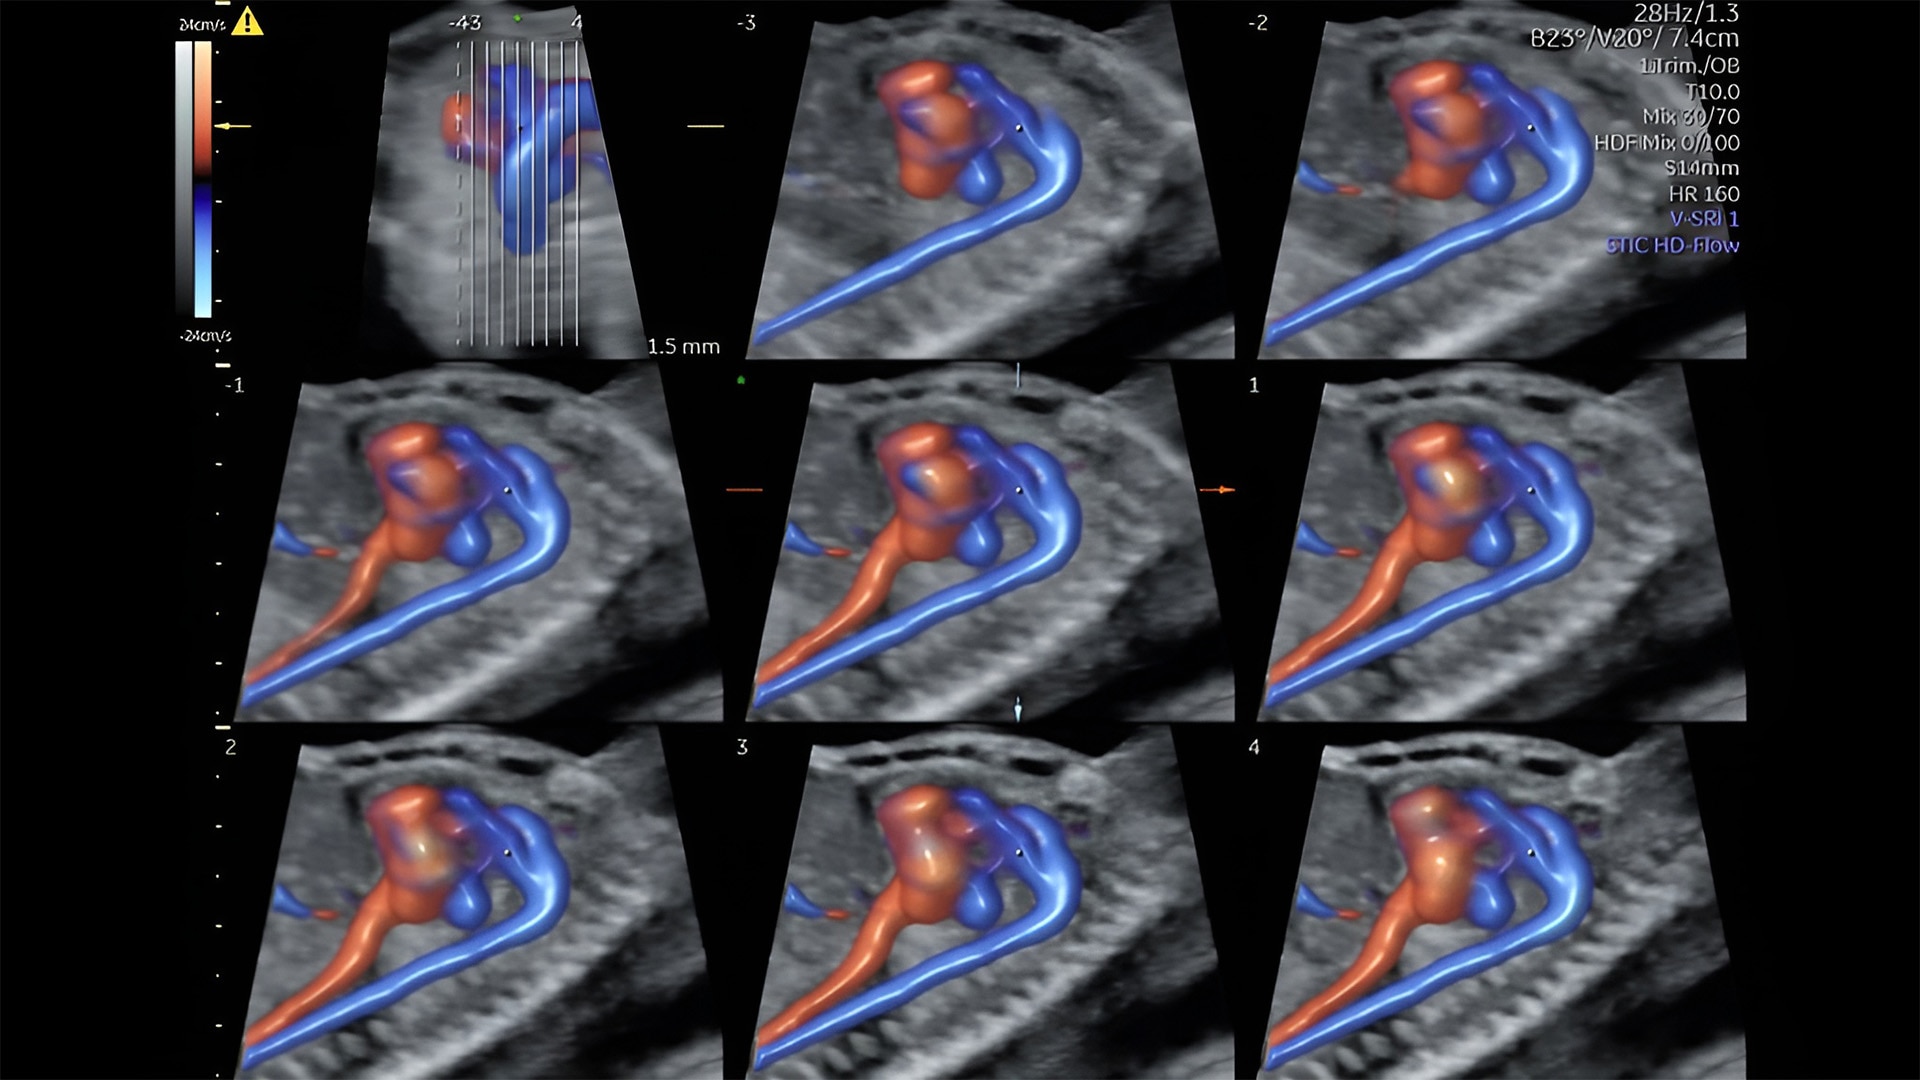

Fetal heart evaluation

Get to the heart of the matter

Identifying fetal cardiac abnormalities earlier means you can intervene sooner, plan for delivery, and potentially improve outcomes. The Voluson Expert 22 provides a full solution of progressive tools, to help distinguish the tiniest structures with stunning clarity to provide patient answers faster.

Fetal heart assessment

Detect, diagnose, and monitor with confidence using Radiant and fetalHQ